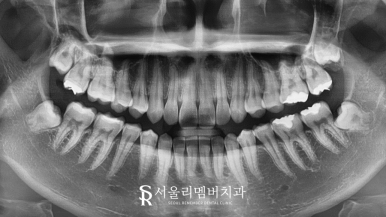

실제 초진 사진을 살펴본 결과

정면에서는 심하지 않은 삐뚤어짐을 확인되었는데요.

측면에서 보면 그 정도가 심한 것을 볼 수 있습니다.

수평피개량이 크게 나타나 툭 튀어나와 있는

돌출의 형태를 갖고 있었습니다.

악궁의 형태는 크게 삐뚤어진 곳은 없었지만

앞니 부근이 약간 틀어진 것으로 확인되네요.

수직, 수평 피개량도 정상 범주에 들어왔으며

정면에서 봤을 때 정중선도 알맞게 잘 맞고 있습니다.

악궁의 형태도 훨씬 긴밀하고 둥근 모습으로

고르게 자리 잡혀 있는 것을 볼 수 있네요.

심미성은 물론이며 바이트 체크를 진행한 결과

교합도 정말 많이 개선이 되었는데요.